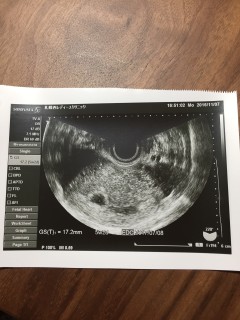

胎嚢10.8mm。 下腹部痛があるたまゆっくり休息しております。

胎嚢のみ確認できました。 前回生理開始日から6週だと思っていたら「現在5週です」との事。 1週間前の診察では影も形も見えず、子宮外妊娠かも…と思っていたので安心しました。

胎嚢(約9mm)確認できました。 現在5週0日目☆ 先生から非常に順調ですと言われて嬉しかったです。スクスク育ってほしいです!